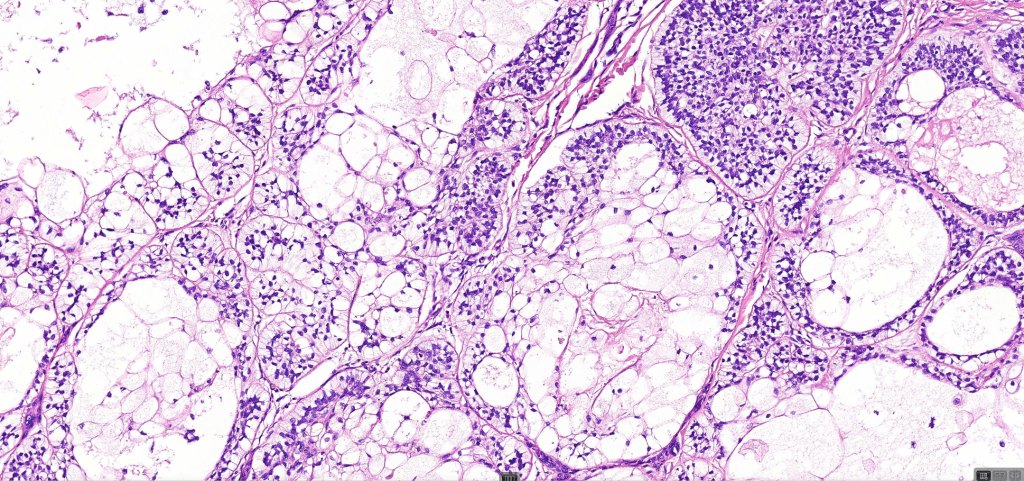

•Both epithelial & fibrous stromal components

•The tumor commonly arises from the epidermis

•The epithelial component is composed of uniform small, basophilic devoid of desmosomes

•Peripheral palisading

•Retraction artifact with stromal mucin

•Pseudoglandular appearance

•A wide variety of histological variants are possible including nodular, nodulocystic, ulcerative, superficial, micronodular, infiltrating/infiltrative, keratotic, basosquamous, pigmented, morpheaform, keloidal, clear-cell, signet-ring cell & granular cell variants, BCC with monster cells, BCC with metaplastic features, BCC with matricial differentiation, basomelanocytic tumor (see separate blog), BCC with thickened basement membrane, BCC with carcinoid-like nuclear palisading & these are illustrated below